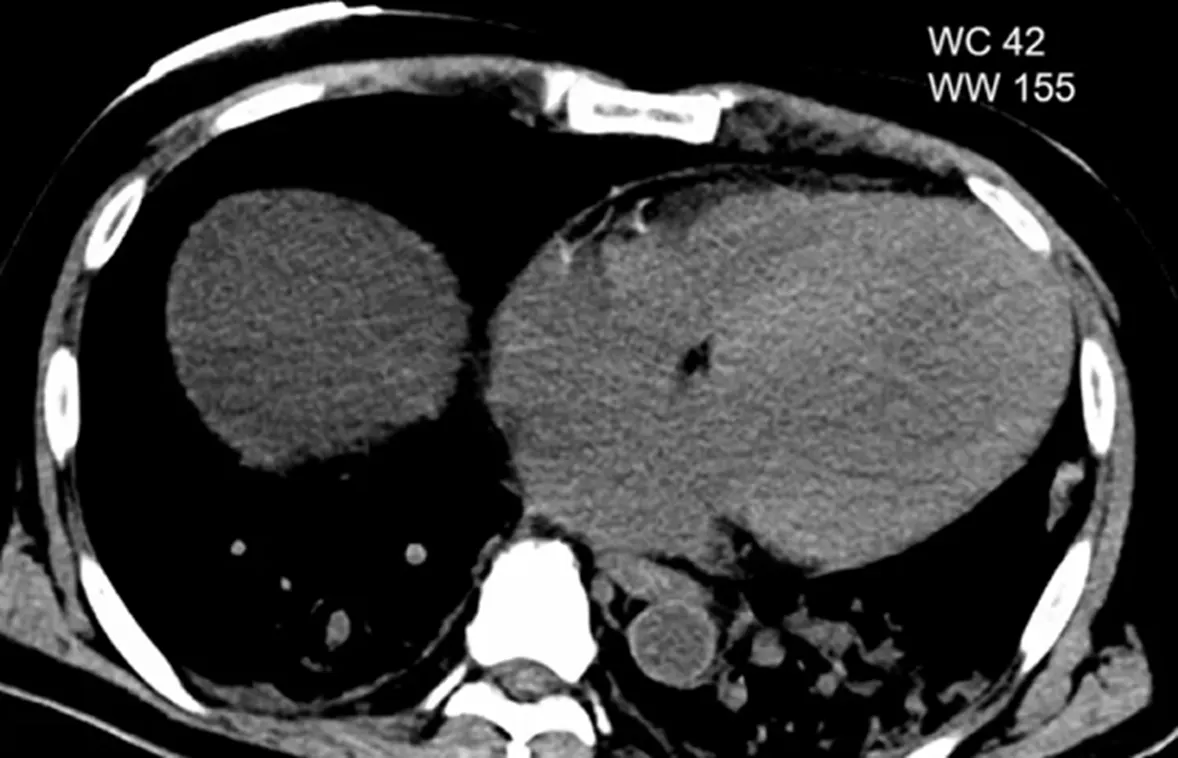

Case 6

•

M/76

C/C: epigastric pain

Hx: BPH, CAOD, COPD, HTN, Aortic stenosis s/p AVR

Lab

WBC 18k (74.1%) , CRP 0.5

AST/ALT 137/74, T.bil/D.bil 1.7/0.5 ALP/rGT 36/861

GB attenuation 높아보임 - Acute cholecystitis with sludge

Next day: revisit ER

C/C : Abdominal pain aggravation , dyspnea

WBC 25k (90.6%) ß 18k (74.1%)

CRP 12.3 mg/dL

Hb 10.9 (4PM) ß 11.5 (1PM) ß 12.9 (9AM) ß 14.7 (1day ago 7AM)

PT(INR) 4.34

Next day: repeated CT

알고 보니 hemobilia 환자

Hemorrhage 가 시간에 따라 attenuation 달라져서 .. Layered pattern

Contrast agent 가 Kidney function 안좋을때 bile excretion 도 함

Hemorrhagic cholecystitis

Rare, life-threatening condition that can lead to GB perforation

End stage of acalculous cholecystitis

Necrosis of the gallbladder wall & pseudoaneurysm formation of the cystic artery

Subsequent rupture and acute bleeding into the gallbladder

Acknowledged causes: blunt trauma, bleeding tendency, GB malignancy

Symptoms easily confused with acute calculous cholecystitis

+hemobilia / hematemesis as blood drains into the GI tract

Biliary stones or impacted sludge may mimic hemobilia and can present a diagnostic pitfall – clinical correlation is necessary